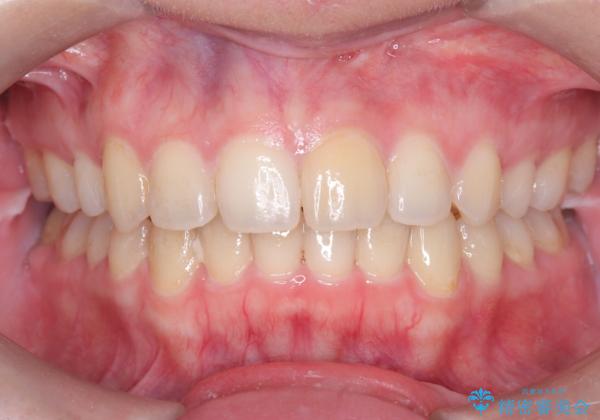

矯正後の後戻り インビザラインで改善

- 前歯のガタツキが気になると来院されました。

マウスピース矯正治療を選択しました。

前歯のガタツキを改善する治療法として、マウスピース矯正が適していることが多いです。

マウスピース矯正は、金属製のブラケットやワイヤーを使用せずに、透明なマウスピースを装着して歯を移動させる方法です。そのため、目立たず、痛みも少ないです。